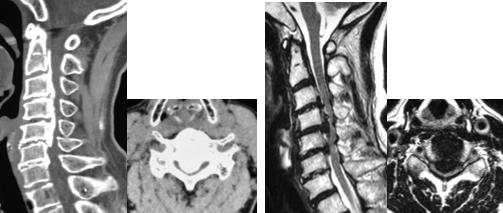

頚椎椎弓形成術

対象となる疾患は、頚椎症性脊髄症、頚椎後縦靭帯骨化症、頚椎椎間板ヘルニア、脊椎腫瘍などです。後方から椎弓を開いたり削除したりして、脊髄を後方にシフトさせることで除圧します。頚椎症性神経根症では、障害されている神経根の部分のみ骨を削ることもあります。

片開き式脊柱管拡大術

頚椎椎弓形成術の代表的な手術法に、片開き式脊柱管拡大術があります。ご高齢の方に対しても、安全で安定した成績が報告されている優れた術式です。手術は首の後ろを切開して、椎弓の両側に骨の溝を掘り、扉を開くように脊柱管を拡大します。開いた椎弓は再度閉じないように糸で固定したり、金属性のプレートで固定します。通常、手術翌日より座位や歩行訓練を行います。手術後のカラーは、病態により装着を考慮します。

-

(左)術前のMRIでは、全体的に脊柱管内の狭窄があります。(中)片開き式脊柱管拡大術を施行し、金属性のプレートで椎弓を固定しています。(右)手術により脊柱管が拡大され、神経症状が改善しています。